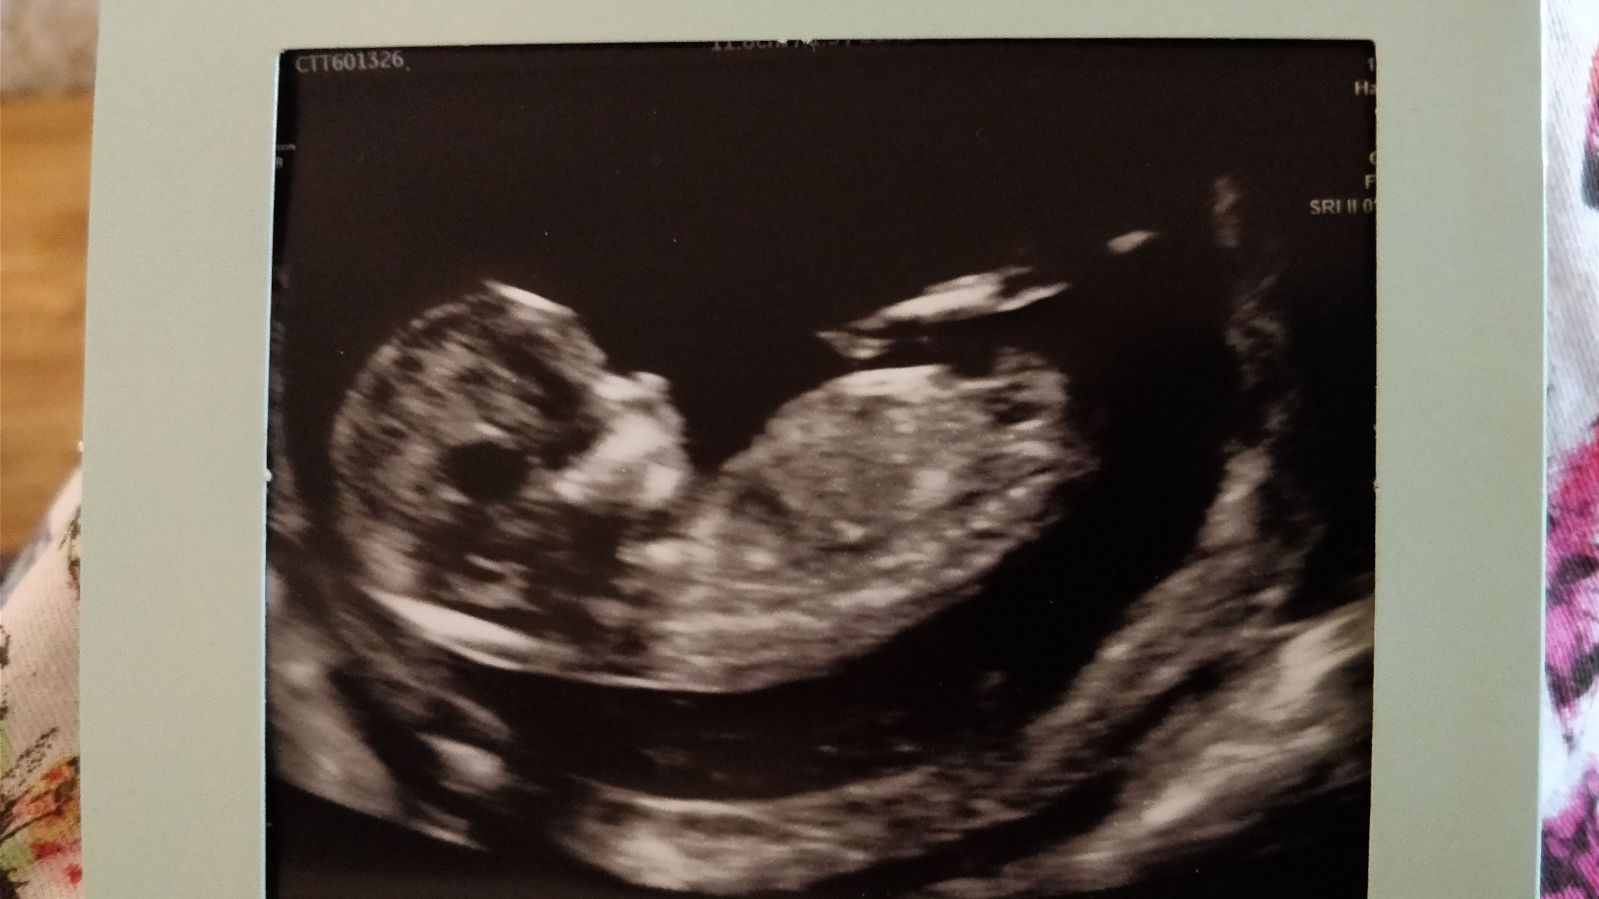

Guessing girl :)

Girl

I‘m seeing boy, esp. for 13 weekshttps://uploads.tapatalk-cdn.com/201...f5b10b4cd4.jpg

Hard to say if the bump is actually attached to the body though. If so, deffo boy:D